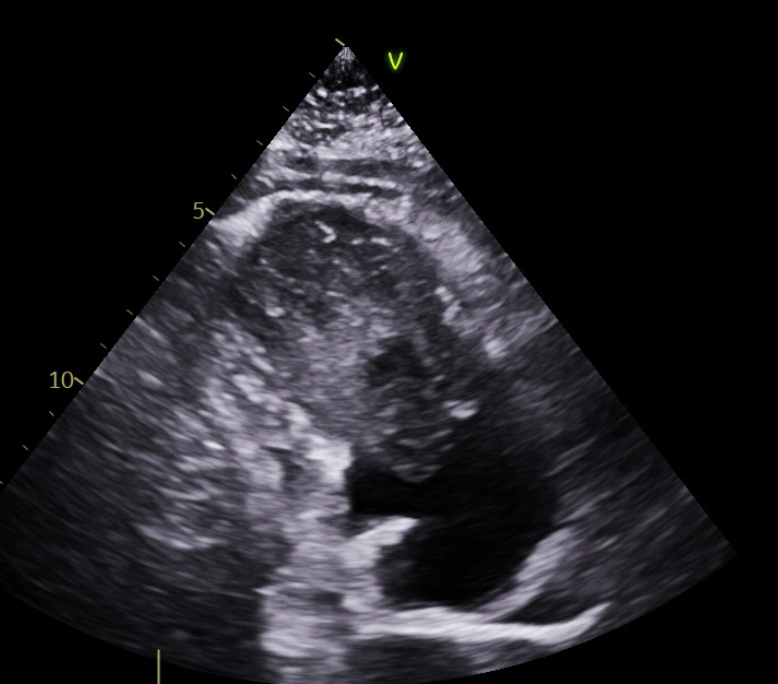

An electrocardiogram showed normal sinus rhythm with nonspecific T-wave changes. His blood pressure was normal. Initial blood work showed mild hyperbilirubinemia, thrombocytopenia, elevated BNP and D-dimer. A CT angiogram of pulmonary artery showed a 7.5 x 4.6 cm mass arising from the right ventricle (RV). A transthoracic echocardiogram (TTE) showed right atrial (RA) and RV dilation with a large mobile heterogeneous mass taking up most of the ventricular cavity and prolapsing into the right atrium during systole, obstructing flow through the tricuspid valve with 45% of Left ventricular ejection fraction (LVEF). A cardiac MRI confirmed heterogenous RV mass with late gadolinium enhancement, attached to inferior wall of the RV causing significant compromisation RV function.

Patient underwent a TTE guided endomyocardial biopsy which confirmed diagnosis of biphasic synovial sarcoma with SS18 rearrangement. The patient was started on doxorubicin and ifosfamide. However, he had adverse reaction from ifosfamide. PET scan did not show any evidence of local or distant metabolically active metastasis. At this point patient’s liver function test has improved. After multidisciplinary discussion patient was planned to continue doxorubicin therapy as an outpatient pending final surgical decision after recovery from acute rehabilitation. RV mass reduced in size on subsequent TTE. Patient is currently under evaluation of surgical resection or advance therapy.